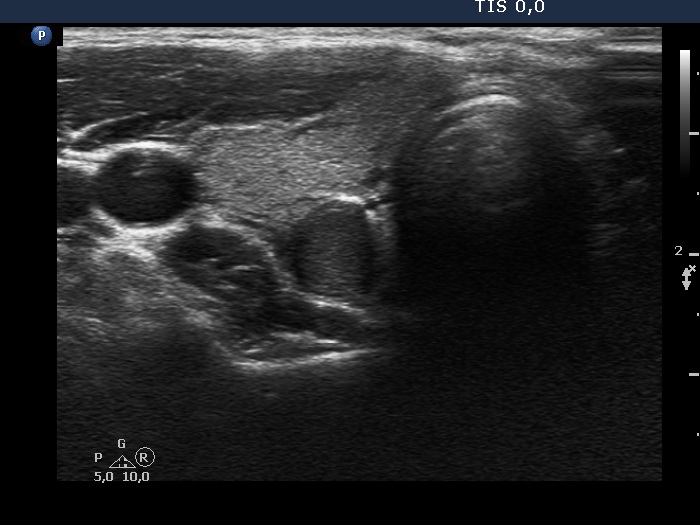

Ultrasonography. The thyroid was echonormal and had numerous discrete hypoechoic areas. The largest one located in the dorsal part seemed to be a pathological nodule at first sight. This lesion showed taller-than-wide shape and had blurred borders. Considering the presence of other, similarly hypoechoic areas in the thyroid, this lesion may be also the presentation of the underlying thyroiditis.

Cytology of the lesion in the right lobe resulted in Hashimoto's thyroiditis.